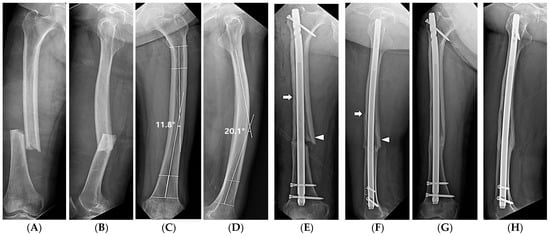

| Lateral bowing, ° | 14.7 ± 5.9 (2.4–24.8) | 7.9 ± 6.5 (0.2–21.9) | <0.001 b |

| Anterior bowing, ° | 16.6 ± 4.2 (9.7–25.1) | 13.0 ± 7.8 (1.0–29.5) | 0.008 b |